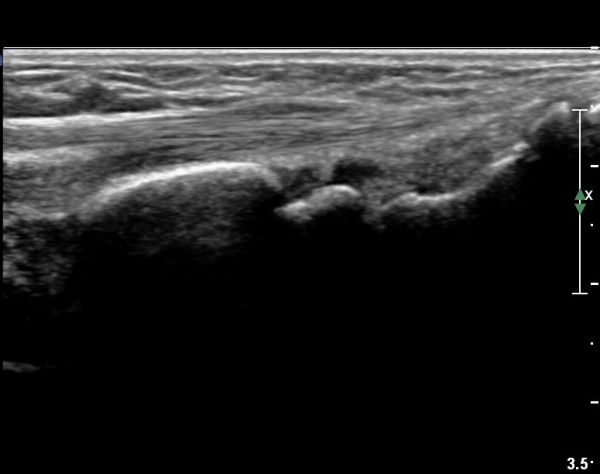

ŽÃËÀÚ¸¦ ¾à°£ ¸»´ÜÀ¸·Î À̵¿ÇÏ´Ï Àå, ´Ü¿äÃø¼ö±Ù½ÅÀü°Ç ºÎÁ¾°ú ÀÌ ½ÅÀü°Ç Ç¥ÃþÀ¸·Î ÁÖÇàÇÏ´Â

À幫Áö½ÅÀü°Ç(EPL)ÀÌ °üÂûµÈ´Ù(»çÁø 4, 5).